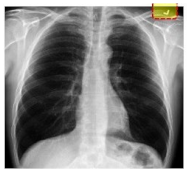

The ROI was extracted from the CXR image to extract the desired information from the image. The ROI area is outlined by a locality primarily covering the lung region to obtain vital information. The ROI area is marked by a rectangle and with the help of logical indexing, the inside area of the region is extracted. Table 2 shows the different pre-processing stages. For example, the unwanted marks in the normal and COVID-19 groups were removed in the first stage (ROI). The CXR images utilized in this examination were gathered from three different sources, which may differ in feature or dimensions. To address this issue, all the images were resized to 300 × 300 before applying any operation on the images. The following Table 2 shows the comparison of original and COVID-19 images.

Table 2. Proposed image processing: original, ROI, and RGB to gray.

Image CategoryOriginalROIRGB to GRAY

NormalElectronics 11 04053 i001Electronics 11 04053 i002Electronics 11 04053 i003

COVID-19Electronics 11 04053 i004Electronics 11 04053 i005Electronics 11 04053 i006